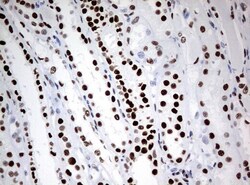

- Submitted by

- Invitrogen Antibodies (provider)

- Main image

- Experimental details

- Immunohistochemical staining of paraffin-embedded Carcinoma of Human kidney tissue using anti-ZSCAN18 mouse monoclonal antibody. (UM500081; heat-induced epitope retrieval by 10mM citric buffer, pH6.0, 120°C for 3min)